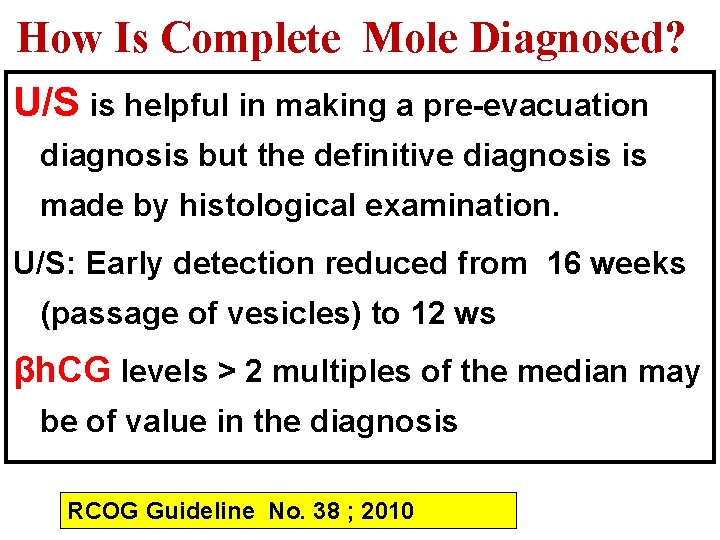

How Is Complete Mole Diagnosed? U/S is helpful in making a pre-evacuation diagnosis but the definitive diagnosis is made by histological examination. U/S: Early detection reduced from 16 weeks (passage of vesicles) to 12 ws βh. CG levels > 2 multiples of the median may be of value in the diagnosis RCOG Guideline No. 38 ; 2010

U/S& βh. CG Definite diagnosis on first U/S examination ØU/S alone: 68% ØU/S + βh. CG > threshold of 82, 350 m. IU/m. L: 89% Disaia &Creasman Clinical Gynecological Oncologym 7 th edd. 2007